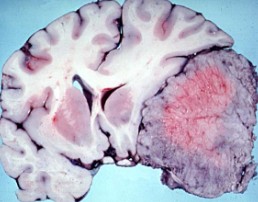

脑瘤图片

脑瘤一般可大略分成脑原发性肿瘤及其他部位(如肺、大肠等)转移至脑部的转移性肿瘤。如不适合做磁振造影检查,在影像检查部份,可做电脑断层应可初步判断。但不论是磁振造影或是电脑断层检查,都只能确认脑部是否有构造上的异常(如是否有异常肿块).